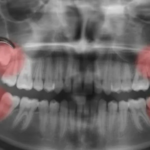

Quais os riscos na extração do siso? Dentista tira dúvidas

Jovem morreu com infecção após retirar dente em SP.

Considerada por muitos como um procedimento corriqueiro e necessário no tratamento dentário, a extração dos dentes do...